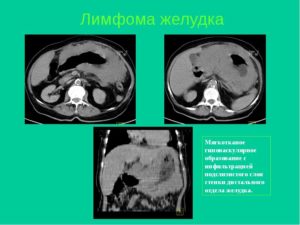

- Псевдолимфома. Характеризуется лимфоидной инфильтрацией слизистой оболочки и подслизистого слоя желудка. Протекает доброкачественно, в некоторых случаях наблюдается малигнизация.